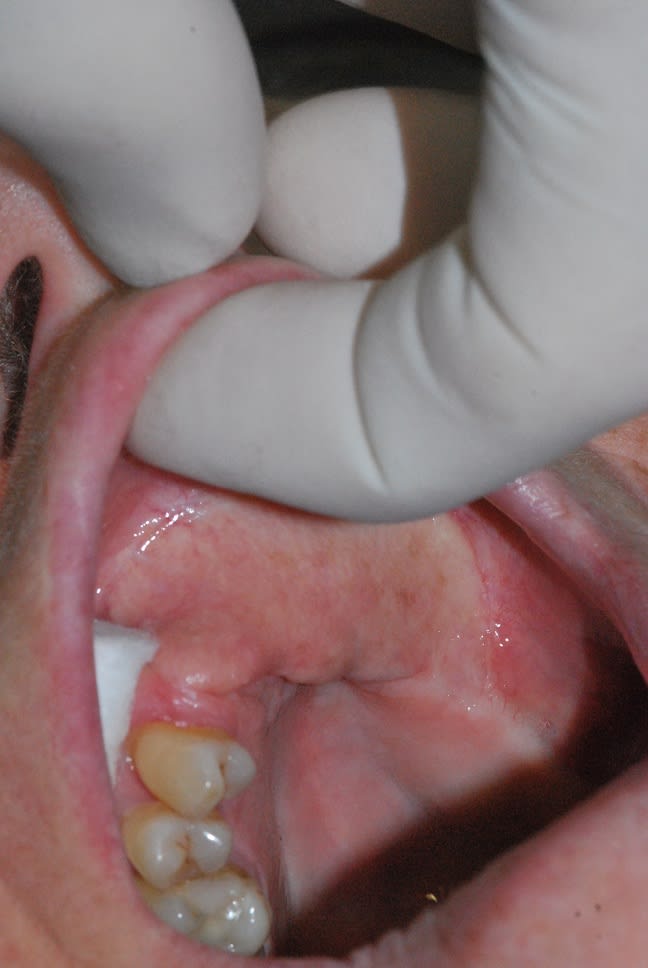

j'aimerais que certains qui ont plus d’expérience que moi puisse me donner des conseils de manière à faire au mieux, pour traiter cette patiente qui a été opérée pour un cancer. la muqueuse au niveau de la crête est mobile, et dépressible.

le maxillo m'a dit qu'il était encore trop tôt pour envisager une nouvelle chirurgie réparatrice